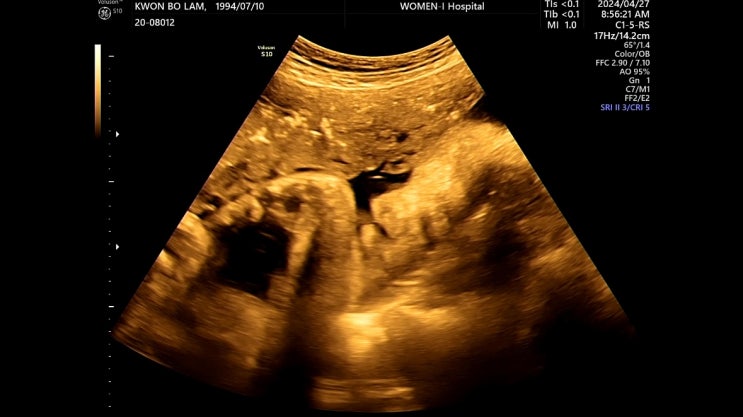

임신 37주 | 대구 여성아이병원 마지막 정기검진 제왕절개수술 안내사항, 입원 준비물 및 진료비

이런 날이 오긴 오는구나... 마지막 진료 보는 날 ㅡㅠㅠㅠㅠㅠ 믿을 수 없는 현실..ㅎ 임신 후기부터 빨리...

임신 34주 | 대구 여성아이병원 정기검진+진료비(태아 몸무게 늘리기 성공!)

32주 이후에 2주만에 다시 내원하는 날~ 특별한 진료는 없고 일반 초음파랑 소변검사만 한다 오랜만에 오빠...